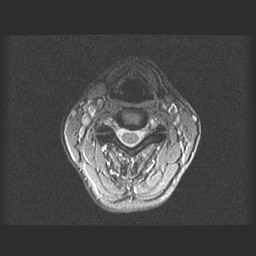

Lage Wervel Zuil